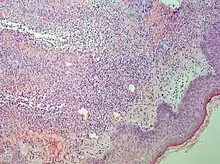

| Sweet syndrome lesions with the classical form of the dermatosis. | |

Sweet syndrome (SS), or acute febrile neutrophilic dermatosis,[1][2] is a skin disease characterized by the sudden onset of fever, an elevated white blood cell count, and tender, red, well-demarcated papules and plaques that show dense infiltrates by neutrophil granulocytes on histologic examination.

Studies show a moderate neutrophilia (less than 50%), elevated ESR (greater than 30 mm/h) (90%), and a slight increase in alkaline phosphatase (83%). Skin biopsy shows a papillary and mid-dermal mixed infiltrate of polymorphonuclear leukocytes with nuclear fragmentation and histiocytic cells. The infiltrate is predominantly perivascular with endothelial-cell swelling in some vessels, but vasculitic changes (blood clots; deposition of fibrin, complement, or immunoglobulins within the vessel walls; red blood cell extravasation;inflammatory infiltration of vascular walls) are absent in early lesions.Perivasculitis occurs secondarily, because of cytokines released by the lesional neutrophils. True transmural vasculitis is not an expected finding histopathologically in SS.